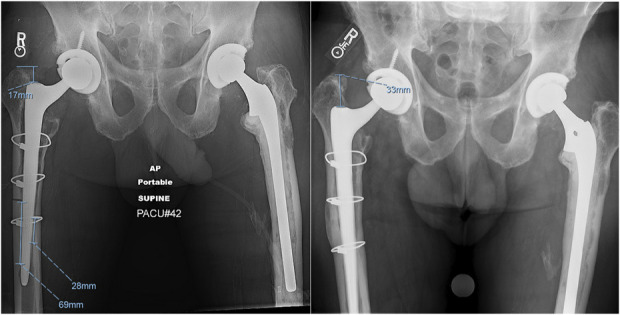

Methods: This is a single-center retrospective cohort study of a prospectively collected database including all patients who received a TSTS from 2016 to 2020. Data collected include surgery type, presence of an ETO, and stem specifications. Radiographs were reviewed to analyze cortical contact and postoperative subsidence. Pearson's correlation coefficient was used to determine the association between contact length and subsidence.

Results: This cohort consisted of 299 hips, and 66 hips necessitated an ETO at the time of TSTS. Patients who required an ETO were more likely to subside (2.5 ± 0.2 mm vs 5.0 ± 0.7 mm, p < 0.001) and were more likely to subside >5 mm (32.3% vs 14.5%, p = 0.001). After controlling for other variables, an ETO was an independent risk factor for significant subsidence (adjusted OR: 3.4, p = 0.02). Contact length below the ETO was inversely related to stem subsidence (correlation coefficient of -0.26; p = 0.037), and multivariable logistic regression demonstrated bicortical contact > 30 mm to be a protective factor for significant subsidence (adjusted OR: 0.12, p < 0.001). Patients who received an ETO had a higher aseptic rerevision rate than patients who had a TSTS implanted without an ETO (16.1% vs 6.6%, p = 0.018).

Clinical relevance: An extended trochanteric osteotomy is an excellent technique to gain direct visualization of the femoral canal. However, it is not without its associated morbidity and postoperative complications, specifically stem subsidence. The results of this study suggest that when preparing for a TSTS after an ETO, careful consideration should be taken to confirm 3 cm of cortical engagement below the transverse limb of the ETO. The scaffolding technique, which prioritizes stem preparation followed by ETO closure, facilitates achieving sufficient cortical contact in the intact canal below the ETO segment. Consideration for intraoperative radiographs to confirm appropriate contact length and location may ensure sufficient fixation that will minimize the risk of postoperative stem subsidence.